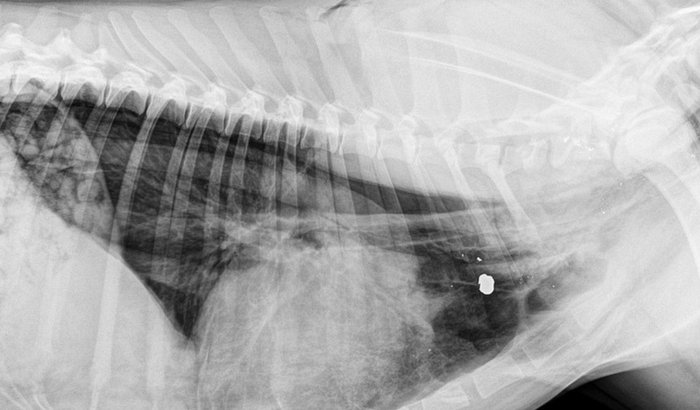

Pessoal, sobre os cachorros que estão por aqui, todos sabem que não são meus, abandonaram a cadela grávida e a gente sendo humano trata eles, sendo que não são nossos. mas na semana passada algum desumano teve a capacidade de dar um tiro de 22 em um deles, o cachorro estava agonizando, eu levei no veterinário em Ernestina e tive este gasto se alguém quiser colaborar de alguma forma fico grato.